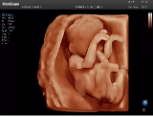

4容積探頭

積探頭是在二維圖像的基礎(chǔ)上,將連續(xù)采集的空間分布位置,經(jīng)過計算機重建算法,從而獲得完整的空間形態(tài)。

適用于:胎兒面部、脊柱和肢體等。

優(yōu)勢特點:快速獲取、掃查連續(xù)均勻、解剖結(jié)構(gòu)顯示為容積數(shù)據(jù)、準確進行容積測量。